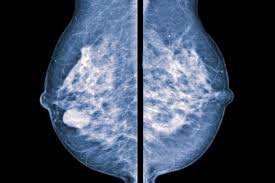

Η μαστογραφία είναι ιδιαίτερα σημαντική και έχει πρωταγωνιστικό ρόλο-κλειδί στην έγκαιρη διάγνωση του καρκίνου του μαστού σε αρχικά στάδια, καθώς μπορεί να διαπιστώσει την ύπαρξη του 1-3 χρόνια νωρίτερα από την εκδήλωση κλινικών συμπτωμάτων.

Η δυνατότητα ρύθμισης της ποιότητας της εικόνας μέσω της χρήσης Η/Υ αυξάνει σημαντικά τη δυνατότητα ανίχνευσης μικρών όγκων για όλες τις γυναίκες, ειδικότερα, όμως, για γυναίκες με μαστούς αυξημένης πυκνότητας (ινοκυστικούς) γυναίκες κάτω των 50 ετών και γυναίκες προ ή περί εμμηνοπαυσιακές.

Παρέχεται σημαντική δυνατότητα ανίχνευσης μικροαποτιτανώσεων που μπορεί να υποκρύπτουν πρώιμο καρκίνο.